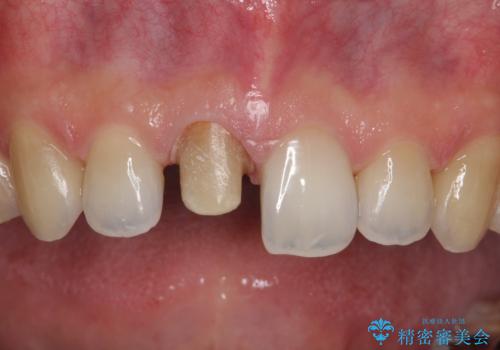

【前歯の被せ物】オールセラミッククラウン(エクセレント)

- 空隙歯列と前歯の変色を主訴に来院されました。

空隙歯列を矯正にて改善した後に歯冠修復を行なっております。

上顎前歯は根管治療後にオールセラミッククラウン(エクセレント)で修復を行なっております。

オールセラミッククラウン(エクセレント)では技工士さんの立ち会いのもと、より審美的な修復が可能です。